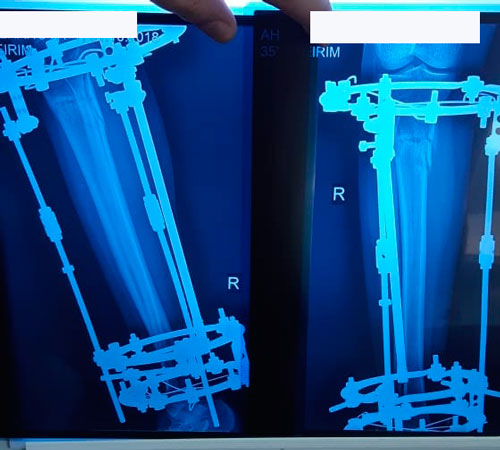

60 дней после операции

gulya1.jpg

gulya.jpg